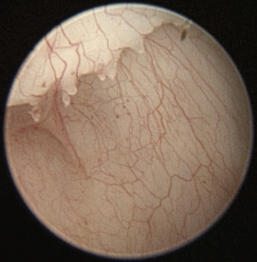

The normal vertical and horizontal ear canal should be pink, and in most animals, the cartilage is flexible; thus the otoendoscope should advance easily down the canal. There can be small amounts of wax in the ear canal. In animals with otitis externa, the changes detected in the ear canal are related to the severity of the ear disease. The first changes noted in the ear canals in cases of acute otitis externa include erythema and glandular hyperplasia (Figure 20-1). The amount of exudate in the ear canal is variable and should be documented, as should its color and consistency. A swab sample from each ear should be obtained for cytologic evaluation. If numerous rod bacteria are noted cytologically or the infection has worsened since the last visit, then a bacterial C/S is indicated. In more severe cases of otitis externa, glandular hyperplasia progresses, resulting in stenosis of the canal, sometimes to the point where the otoendoscope can no longer be advanced into the vertical ear canal. The degree of stenosis and hyperplasia should also be documented. Ulcerations may also be noted, especially in ears secondarily infected with P. aeruginosa. Parasites such as Otodectes cynotis may be visualized rapidly moving about in the ear canal with the video otoscope and are usually found in conjunction with dark brown ceruminous (“coffee ground”) exudate. On occasion, masses or foreign bodies may be seen in the ear canal during the video otoscopic examination.

image

Figure 20-1 Mild erythema and glandular hyperplasia associated with otitis externa are some of the first changes noted in the ear canal.

(Courtesy of Dr. Lynette Cole, The Ohio State University, Columbus, Ohio.)